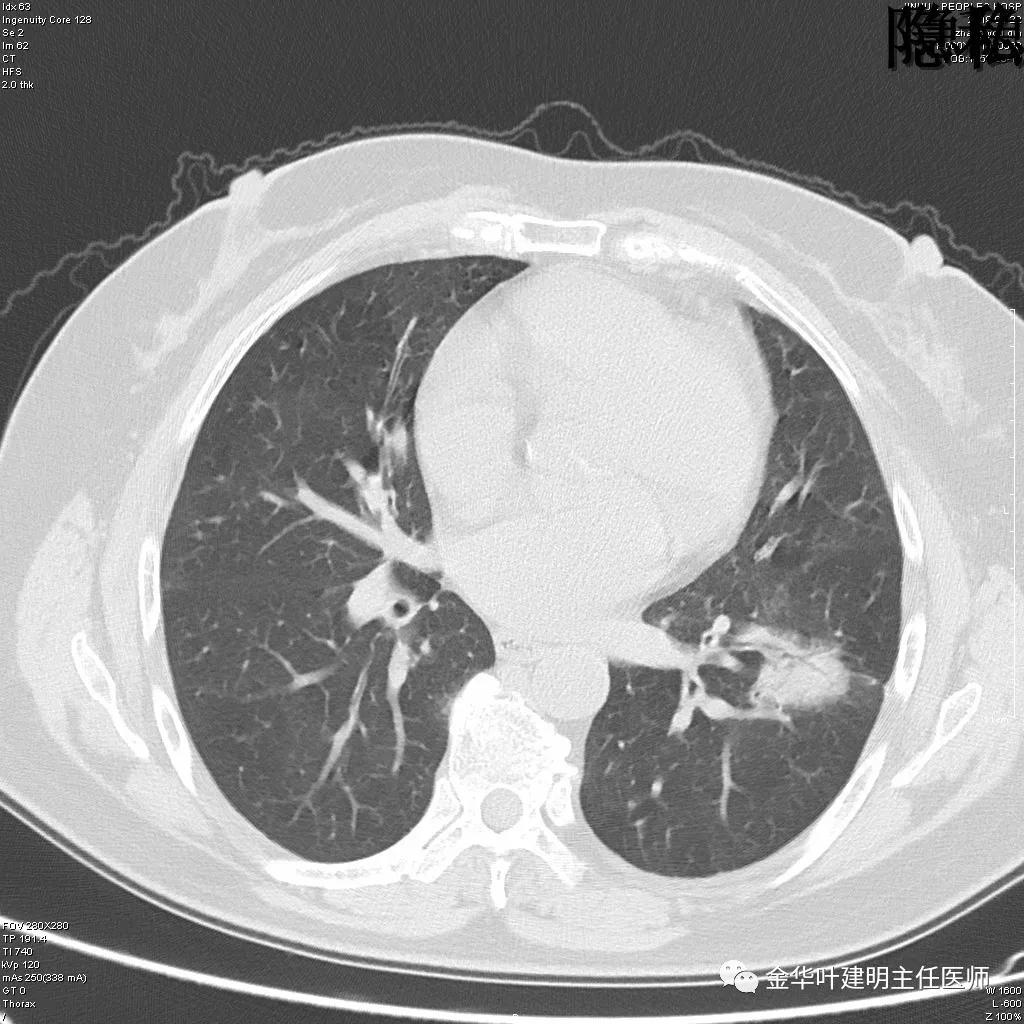

(病例资料2019年)金华的章某,今年60岁,前段时间因为咳嗽,到市区某三甲医院检查,发现她的左肺上叶与左肺下叶都有占位性病变。由于章某有亲戚在我们医院工作,所以在亲戚的指引下,让她来找我。我们予以适当的抗炎治疗,然后复发CT,发现病灶没有任何变化。其中平扫的片子如下:

可见左肺上叶有一占位,是空腔性的,其内有实性密度填充,是比较典型的肺曲菌病的表现,但病灶有点大,长径大于3-4厘米许。

可见左肺下叶比较靠中央的部位也有一病灶,是混合磨玻璃影,偏实性,瘤肺边界清楚,是较为典型的肺癌表现。进一步的靶扫描图像如下:

靶扫描更清晰的显示细节,从影像上看,基本可以断定左下肺的是恶性肿瘤了,而且已经密度较高,长径也在3厘米以上,不能继续观察等待了!